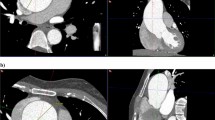

Among those who underwent chest CT (n = 34), the most common findings in the lung parenchyma were hyperlucent lung parenchyma (n = 17, 50%), pulmonary nodules (n = 17, 50%), and bandlike areas of scarring (n = 19, 56%). Hyperlucent lung parenchyma usually involved < 50% of the lobe and was most common in the right upper lobe (n = 11, 32%). Lung cysts nearly always involved < 50% of a lobe and were most commonly involved the right lower lobe (n = 6, 18%). Both calcified and non-calcified nodules were present. Nine individuals had only non-calcified nodules, four individuals had only calcified nodules and four had both calcified and non-calcified nodules. All nodules were well-circumscribed, smoothly marginated, and round or oval in shape. The calcified nodules were completely calcified and ranged in size from 1 to 6.5 mm. Non-calcified nodules ranged from 1 to 17 mm in size and were completely soft tissue in attenuation. Large non-calcified nodules (10 to 17 mm) were observed in only one individual of our cohort. Interlobular septal thickening was present in four individuals (12%). Incidental, acute lung parenchymal findings in 4 individuals (12%) who had pneumonia at the time of scanning included consolidation and ground glass opacity. Minimal bronchiectasis was present seen in one individual (3%). Tracheal diverticulum and tracheal bronchus were incidental findings in two individuals (6%). One individual (38 year-old non-smoker) had a perihilar, left upper lobe mass (3%), which was biopsied and findings were compatible with primary lung adenocarcinoma. These findings are illustrated in Figs. 2 and 3 and summarized in Table 4.

Chest CT images showing lung parenchymal involvement in individuals with Proteus syndrome. Axial CT images in lung windows show (a) nodules in the bilateral upper lobes measuring up to 17 mm in size (arrows) in a 9-year-old male. An area of cystic change is also noted in the right upper lobe (asterisk); (b) areas of hyperlucent lung parenchyma within the right middle lobe and left lower lobe (arrows) in a 10-year-old male. There is also a cyst in the right lower lobe (asterisk) that abuts a curvilinear band of scarring posteriorly. (c) Axial CT image in soft tissue windows shows a lobulated mass in the perihilar left upper lobe (arrow) in a 38-year-old female nonsmoker, which was found to be primary lung adenocarcinoma on pathology. Overgrowth of the vertebral body and posterior elements of the spine are also noted (asterisks). (d) Axial CT image in lung windows shows subtle interlobular septal thickening (arrows) in the right upper lobe in a 14-year-old female. Skeletal overgrowth involving the posterior spinous elements and right posterior rib are also noted (arrowheads).

Chest CT images in soft tissue windows showing vascular abnormalities in individuals with Proteus syndrome. (a) Axial CT image shows abnormally enlarged right pulmonary veins (arrows) in a 15-year-old male. (b) Axial CT image shows a filling defect in the right lower lobe pulmonary artery (arrow) compatible with a pulmonary embolism in a 34-year-old male. Incidentally, there is also consolidation secondary to pneumonia within the left lower lobe as well as an associated small left pleural effusion (asterisk).

Vascular involvement

More than half of the individuals with chest CTs had pulmonary venous dilation (n = 21, 62%), as shown in Fig. 3. Affected pulmonary veins were diffusely dilated. Right and left pulmonary veins were involved similarly (n = 17 and n = 16, respectively). Ten individuals also had abnormal enlargement of systemic veins: internal jugular vein, subclavian vein, brachiocephalic vein, superior vena cava and the azygos vein. Pulmonary embolism was detected in two symptomatic individuals (6%) on CT angiography (Fig. 3). Mild aneurysmal dilation (diameter 42–43 mm) of the ascending aorta was present in two individuals (6%). The vascular findings are summarized in Table 4.

Pulmonary nodules, areas of hyperlucent lung, and bandlike areas of scarring were present in at least 50% of individuals, which is much greater than the 8–13% described in prior reports8,12,17,29. Although we did not have pathology available for the pulmonary nodules in this study, they are suspected to be hamartomas based on prior published pathology12. In regards to the hyperlucent lung parenchyma, previous studies with pathology found that the areas of hyperlucent lung parenchyma corresponded to panlobular emphysema12,15. However, additional pathological evaluation is needed to further validate this correlation.

Pulmonary venous dilation was present in over half of our cohort. However, systemic venous dilation was less common. Venous dilation in Proteus syndrome is secondary to vascular overgrowth, but it remains uncertain as to why the pulmonary veins are affected more commonly than systemic veins. Vascular anomalies (tumors, malformations) have been previously reported6,8,30, however we did not observe any.